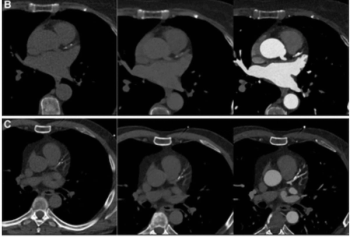

Emerging research on coronary artery calcium scoring for the assessment of coronary artery disease (CAD) suggests the use of virtual non-contrast images from photon-counting CT may lead to a nearly 20 percent reduction in radiation dosing.

Employing quantitative computed tomography, the staging system’s insights on stenosis, ischemia and coronary atherosclerosis may facilitate individualized assessments of heart disease risk.

Computed tomography (CT) findings from over 1,700 patients with stable chest pain reveal that coronary artery calcium (CAC) scores of 0 are associated with a 4.1 percent prevalence of obstructive coronary artery disease (CAD) whereas CAC scores of 400 or higher are linked to a 76.1 percent incidence of obstructive CAD, according to research from a multinational study.